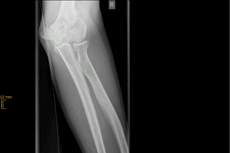

Distale Humerusfraktur

Der untere Anteil des Oberarmknochens bildet einen Anteil des Ellenbogengelenkes, auf dem sich die Unterarmknochen Elle und Speiche als Gelenkpartner bewegen. Frakturen in dieser Region müssen fast ausnahmslos operiert werden.